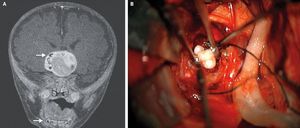

A 4-month-old infant in Maryland was found to have teeth form in his brain as a result of a specific type of rare brain tumor. The child underwent brain surgery to have the tumor removed, during which doctors found that the tumor contained several fully formed teeth, according to a report of the case. After an analysis of tumor tissue, doctors determined the child had a craniopharyngioma, a rare brain tumor that can grow to be larger than a golf ball, but does not spread. Researchers had always suspected that these tumors form from the same cells involved in making teeth, but until now, doctors had never seen actual teeth in these tumors, said Dr. Narlin Beaty, a neurosurgeon at the University of Maryland Medical Center.